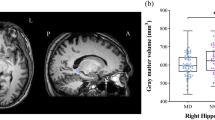

Table 2 presents the volumes of the total hippocampus and its subfields including CA1, CA2/3, CA4, fimbria, GC-ML-DG, HATA, fissure, tail, ML, Para, Pre, and Sub. Among them, CA1-CA4, GC-ML-DG, ML, and Pre were divided into the head and body as well as the whole hippocampus. ANOVA showed that the significant differences were concentrated in the left hippocampus among the three groups. Significant differences were observed in the volumes of the hippocampal head, mainly in the CA1 head, GC-ML-DG head and ML head. After a post hoc analysis, we found that although the whole left hippocampus was significantly smaller in both groups of patients with MDD, only MDD patients with anhedonia displayed significant volume reductions in the left hippocampus head, body, CA1 head, GC-ML-DG head and ML head when comparing to HCs (Fig. 1). No significant difference was found in the volumes of the hippocampal subfields between MDD patients without anhedonia and HCs, either the two groups of MDD patients.

Comparisons of hippocampal subfield volumes between the three groups. Asterisk represents significantly different volume versus HC group after Bonferroni correction. ** p < 0.01; *p < 0.05. Error bar represents one standard error. 1, MDD with anhedonia; 2, MDD without anhedonia; 3, Healthy Controls. CA, cornu ammonis; GC-ML-DG, Granule cell and molecular layer of the dentate gyrus; ML, molecular layer